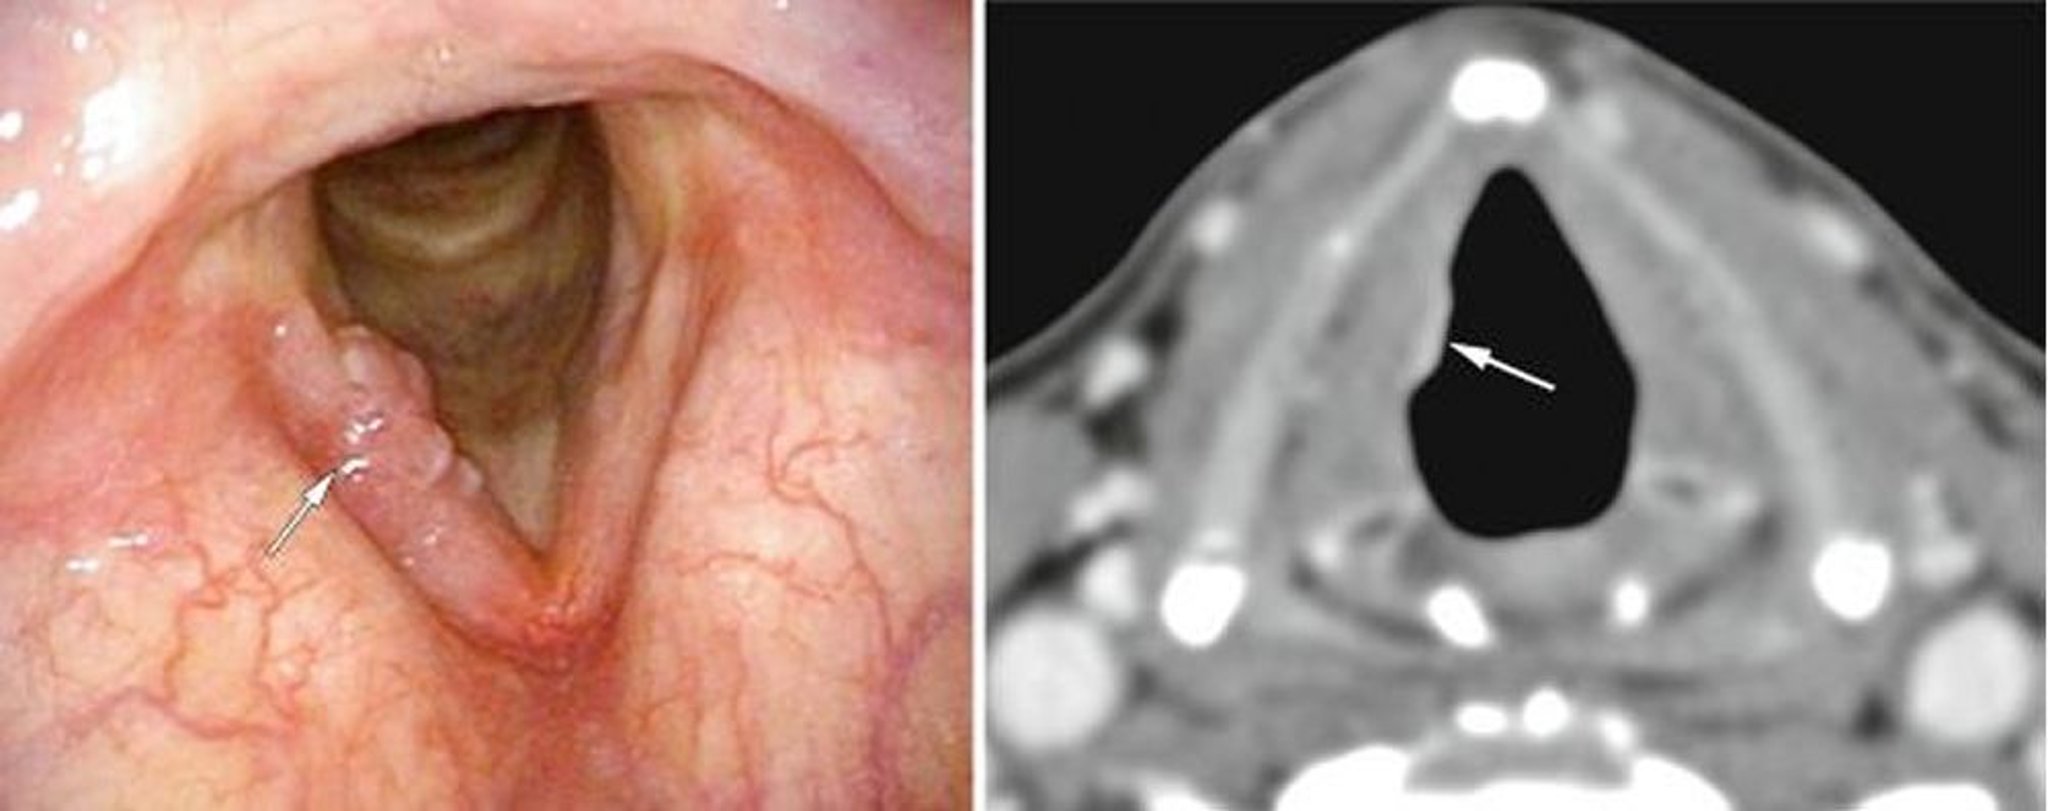

Diagnosis of Laryngeal Cancer

• Laryngoscopy

• Operative endoscopy and biopsy

• Imaging tests for staging

All patients who have hoarseness for > 2 to 3 weeks should have their larynx examined by a head and neck specialist. Some clinicians use a mirror to evaluate the larynx, but most often a flexible fiberoptic examination is done. Any lesions discovered require further evaluation, usually with operative endoscopy and biopsy, with concomitant evaluation of the upper airway and gastrointestinal tract for coexisting cancers. The incidence of a synchronous second primary tumor may be as high as 10% (1).

Patients with confirmed carcinoma typically have neck CT with contrast and a chest radiograph or chest CT. Most clinicians also do PET of the neck and chest at the time of diagnosis.